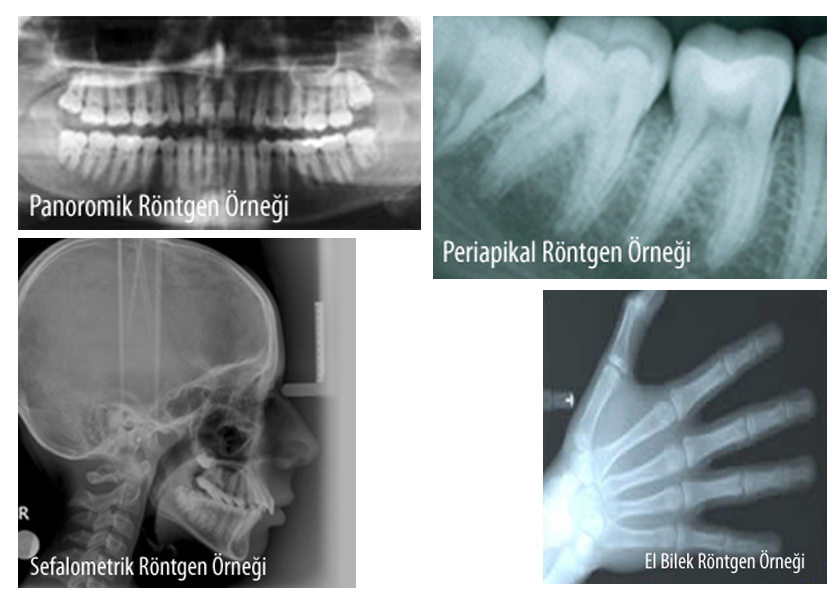

Diş hekimliğinde tanı amacıyla yaygın olarak periapikal röntgen filmlerinden yararlanılır. Periapikal röntgenlerde sadece bir veya birkaç diş grubu görüntülenebilir.

Ağızdaki tüm dişlerin, kemik içindeki oluşumların ve anomalilerin görüntülendiği röntgen filmine ise 'panoromik' röntgen filmi denir. Dijital görüntüleme cihazı ile ortodontik tanı amaçlı kullanılan sefalometrik grafiler, kemik yaşının belirlenmesinde kullanılan el-bilek röntgenleride görüntülenebilir. El -bilek röntgenleri özellikle adli vakalarda kemik yaşının belirlenmesinde yol göstericidir.